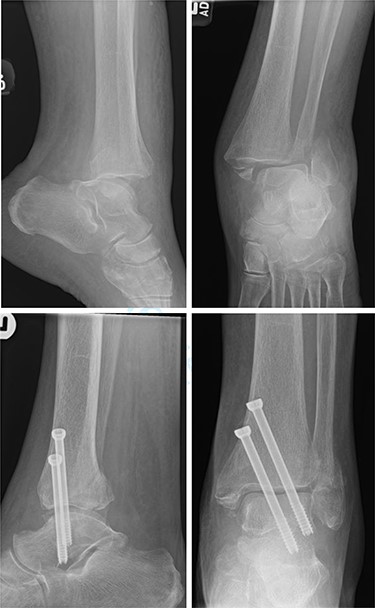

One patient (16.7%) with a bimalleolar (posterior and medial malleoli involvement) fracture had evidence of minor talar shift at 5 months, but no other significant radiological findings. Additionally, the patient reported no pain, and mobility recovered to a preoperative level (Fig. 3).

Top—Bimalleolar ankle fracture with talar shift. Bottom—Radiograph at 5 months showing small amount of talar shift.